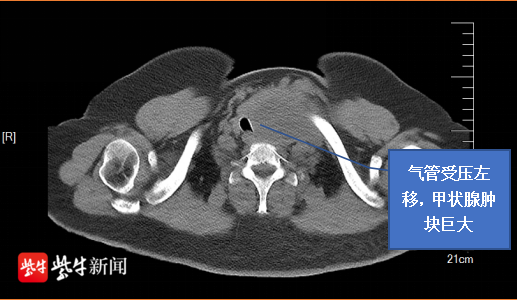

据了解,65岁的曹女士是一位来自泰州的胸骨后巨大甲状腺肿患者,早在10年前就在颈部摸到了肿块,但当时并未重视,近期肿块越来越大,逐渐出现了呼吸困难和吞咽不适的症状。在当地医院检查发现肿块已经超过10cm、并且长到了胸骨后方。由于胸骨后甲状腺肿的手术难度大、风险高、并发症多,患者及家属多方打听后,来到苏大附二院甲乳外科就诊。

经进一步完善检查发现,曹女士左侧甲状腺肿造成了气管明显受压变窄,狭窄部位气管直径仅有10-11mm,属于困难气道患者。该院甲乳外科主任医师蒋国勤告诉记者,甲状腺和胸骨后方供血丰富,术中分离肿块时一旦操作不慎,易伤及组织和血管,造成术中大出血,手术风险极高。